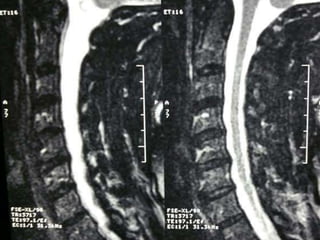

77 year old woman with h/o hand weakness/numbness/ataxia

Prior acdf 14 years ago

Note:the black line directly posterior to the vertebral bodies and relative

Thinning of spinal cord, note normal disc height

Mid-sagittal diameter: width

1:5 ratio leads to necrosis of gray

matter

• Ogino H: Canal diameter, anteroposterior compression ratio

and spondylotic myelopathy of the cervical spine. Spine 1983;

8:1-15

• Cord compression causes ischemia and direct mechanical

trauma